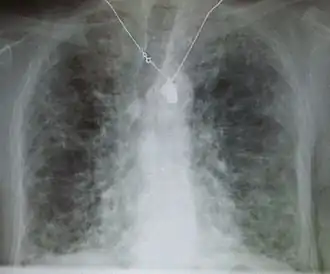

La radiographie du thorax peut être normale ou anormale, et le scanner thoracique montre fréquemment des anomalies caractéristiques[2].